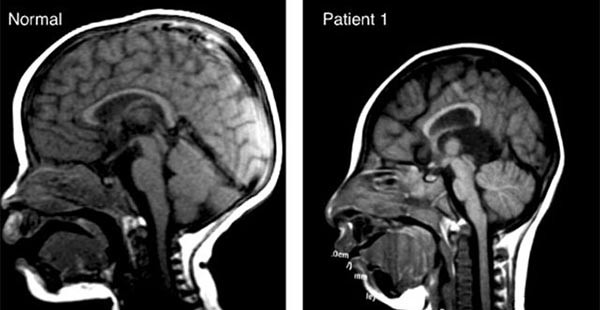

- ▲ 일반인과 '소두증' 환자의 뇌구조 비교사진. ⓒ쿼츠닷컴 보도화면 캡쳐

‘소두증’이란 뇌가 자라지 않는 선천성 질병으로 신생아 때부터 뇌 성장이 제대로 되지 않아 갈수록 운동능력, 지각능력이 크게 떨어진다. 심할 경우에는 생명에도 지장을 준다.